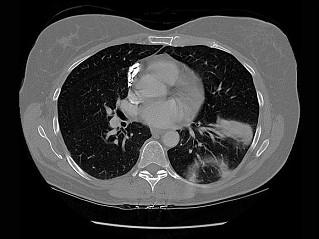

问题 71岁,女,发现颈部淋巴结肿大,胸片和CT检查如图,请选出最可能的诊断 ( )

选项 A、肺癌 B、神经源性肿瘤 C、淋巴瘤 D、淋巴结核 E、结节病

答案 C